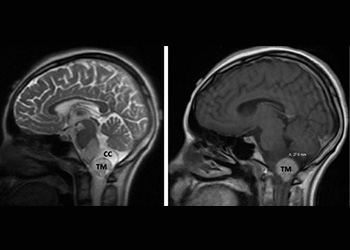

Figure 1. Brain MRI showing tumor mass (TM) with cystic component (CC) and edema (T2-weighted MRI, left) in the lower brainstem and upper cervical cord. Mass […]